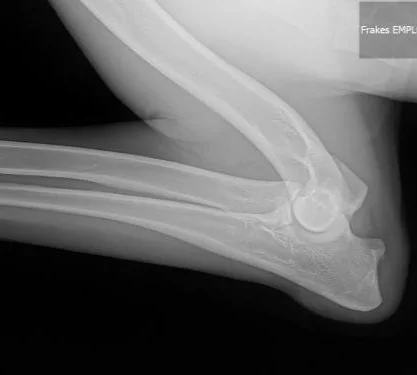

diagnostics